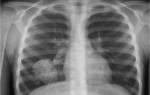

Данной форме характерно формирование больших участков поражения легочной ткани. Патологический процесс может охватывать как одно, так и оба легких. На иллюстрации ниже показана тяжелая форма крупозной пневмонии.